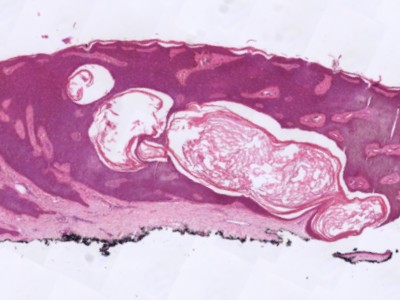

PA:Is niet nodig,

maar soms worden de laesies ingestuurd voor PA omdat ze kunnen lijken op een

melanocytaire laesie. Ook histologisch is het onderscheid te maken door de

aanwezigheid van pseudohoorncysten. En het ontbreken van atypische

melanocytaire cellen.

![Histologie melanoacanthoma (click on photo to enlarge) [source: Kevin Kwee / Afdeling Pathologie MUMC] Histologie melanoacanthoma](../../../pacoupes/thumbnails/melanoacanthoma.jpg) |

ingescande coupe (zoom) |